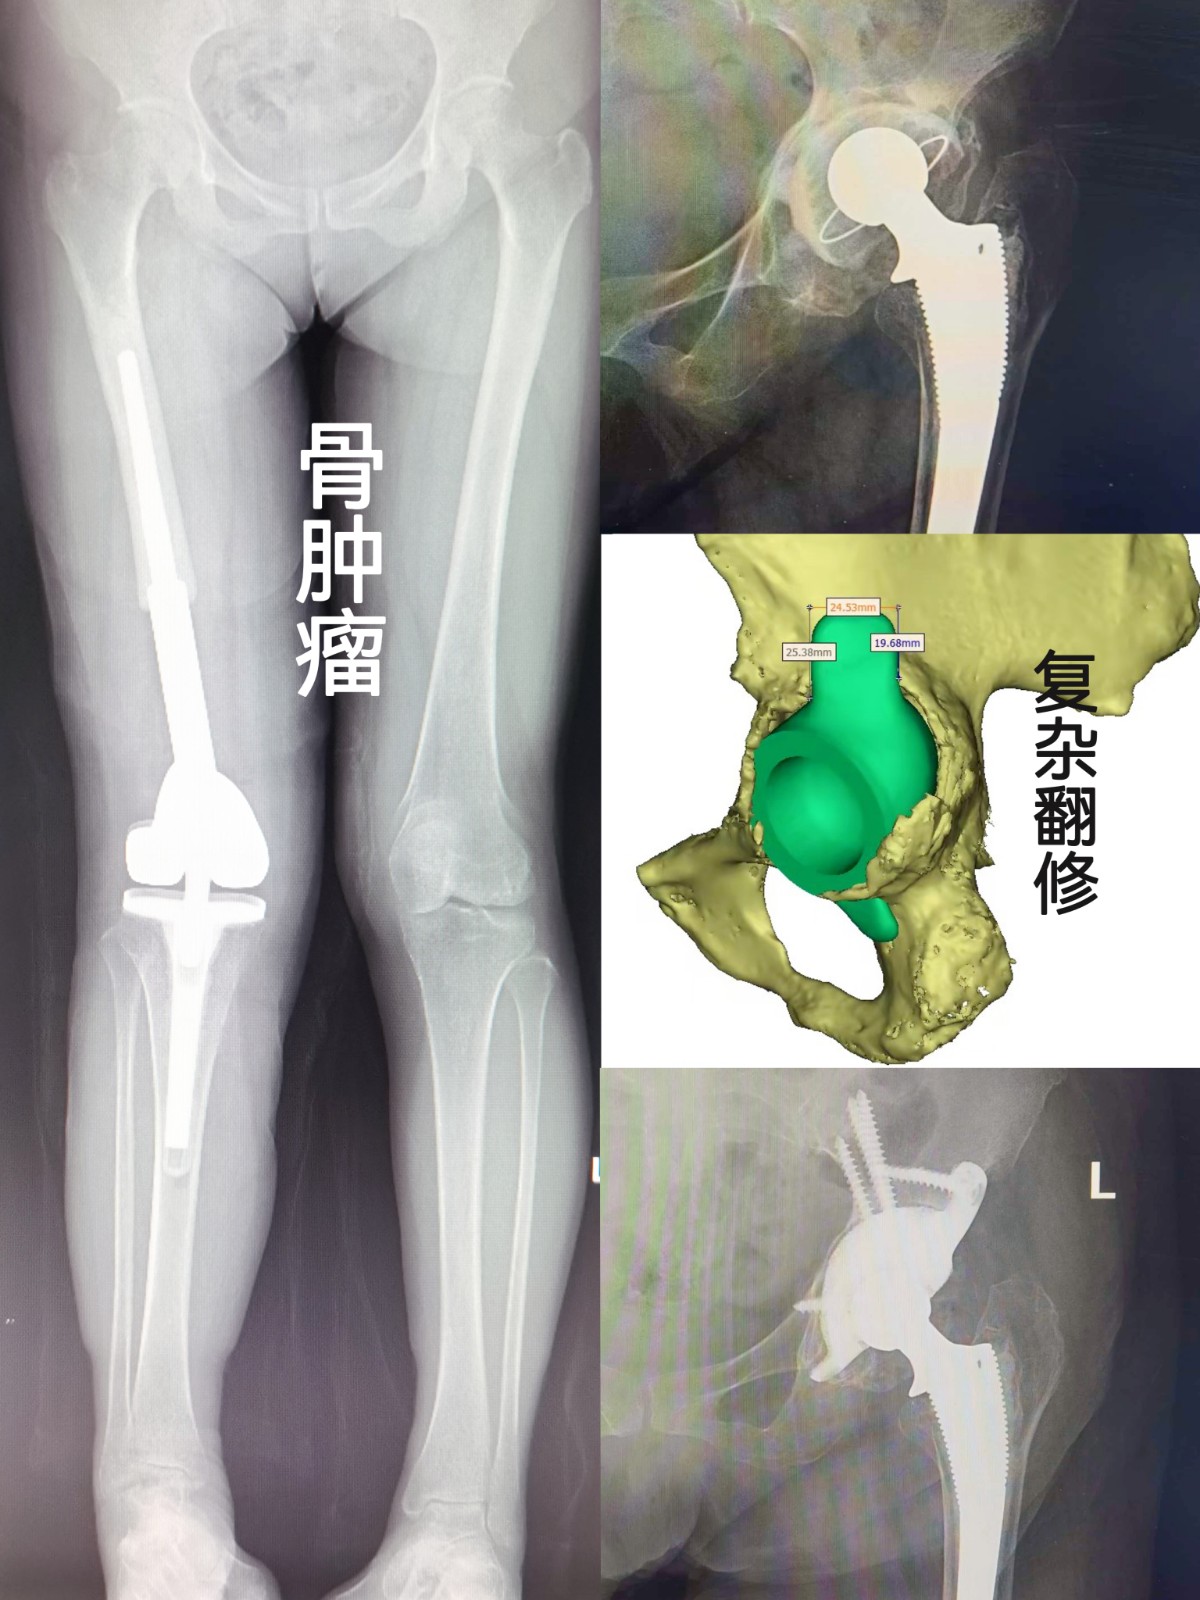

作为本地区创建最早的关节专科,专业化特色明显,关节手术复杂程度及手术量,均为本地区之最;可独立开展各种肩、肘、腕、指、髋、膝、踝等关节的置换及翻修手术,特别擅长复杂髋、膝关节的置换、矫形、翻修,以及保膝阶梯治疗等。科室多年来在骨关节炎、关节畸形、股骨头坏死,类风湿关节炎,强直性脊柱炎性关节病,髋关节发育不良,骨肿瘤,关节周围骨折、脱位,以及关节运动损伤等疾患的治疗中,积累了丰富的临床经验。其中多种技术均为本地区首例独家开展。

复杂髋翻修